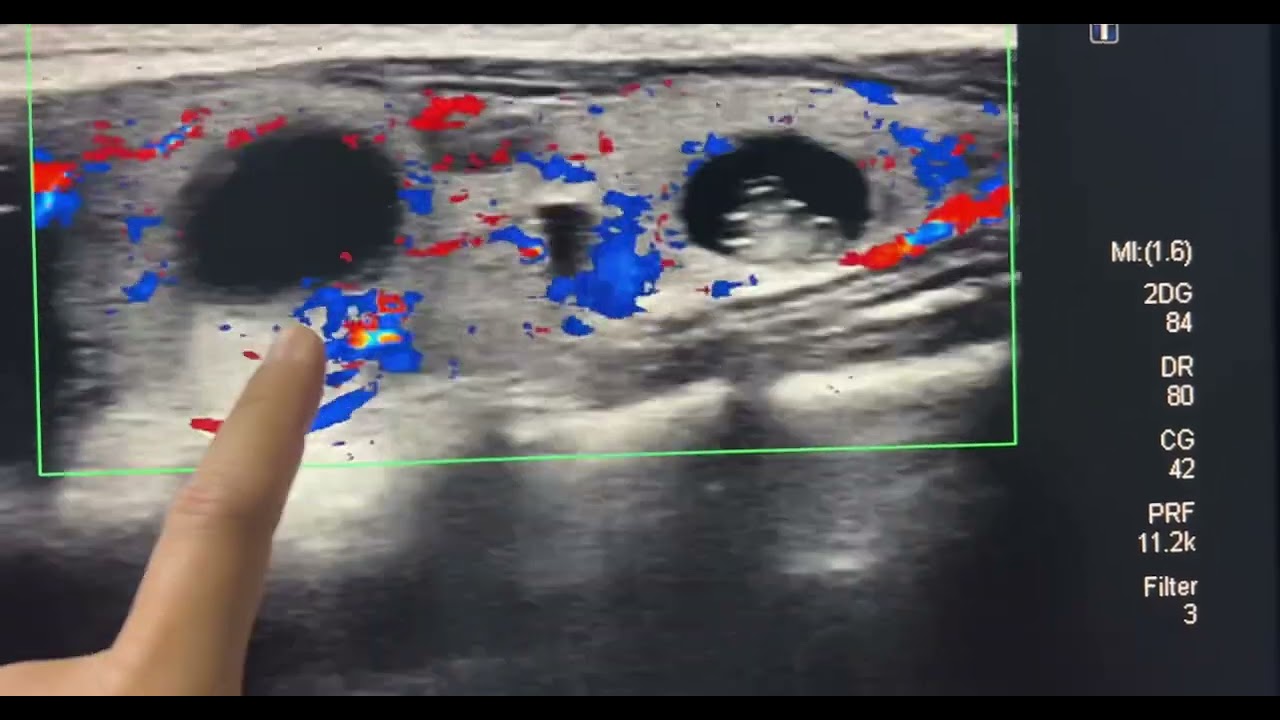

អ្វីដែលយើងជាគ្រូពេទ្យ រកឃើញ គឺទារកមាន សរីរៈខាងក្នុងពោះ កកើតដុំគីសទឹកធំតឹងណែនពេញពោះរបស់ទារក ក្នុងផ្ទៃពោះម្តាយ ( fetal abdominal cyst during pregnancy ) ។

ទារកមានវ័យ 20 សប្តាហ៍ 01 ថ្ងៃ ដែលទារកនេះមាន ដុំគីសធំ - រាងពងក្រពើ - គេមជ្រុងរាងពងក្រពើ និង សារធាតុរាវខាងក្នុងជាទឹកថ្លា ដែលមានទំហំ : 11mm X 130 mm បានកកើតនៅក្នុងប្រហោងពោះទារក(fetal abdominal cysts) ស្រោម ស្តើង កំរ៉ស់ : 1mm ។ ដុំគីសធំក្នុងផ្ទៃពោះទា

រកហើយក្នុងផ្ទៃពោះម្តាយនេះវាបានបង្ហាញ

តាមអេកូសាស្រ្ត ឬ អ៊ុលត្រាសោន ( Échographie or Ultrasound ) ។ ដែលយើងអាចបញ្ជាក់បានពីទ្រង់ទ្រាយនៃដុំគីសទឹកធំនេះវាមានស្រោមរបស់វាផ្នែកខាងលើបានសង្កត់លើ : ក្រះ ថ្លើម ប្រម៉ាត់ ពោះវៀនតូច ពោះវៀនធំមួយផ្នែករុញច្រានទៅផ្អិបជាប់សន្ទះទ្រូង , ស្រោមគីសផ្នែកខាងក្រោយក្រោមរុញច្រានផ្អិបជាប់តាមបណ្តោយឆ្អឹងខ្នង ចង្កេះ និង អាងត្រគាក និង ផ្នែកស្រោមគីសខាងមុខរុញច្រានផ្អិបជាប់ជញ្ជាំងពោះ ខាងមុខនិងសងខាង ។ ដោយសារស្ថានភាពដុំគីសធំបែបនេះ ស្ថិតក្នុងពោះទារកមានវ័យ ២០សប្តាហ៍ ១ថ្ងៃ និងកំរិតនៃបរិមាណទឹកភ្លោះតិចតួច ឬ សឹងតែគ្មានទឹកភ្លោះ ធើ្វអោយចង្អៀតណែន ពិបាករើបំរ៉ាស់របស់ទារក នៅក្នុងប្រហោងស្បូន ទាំងមូល ។ ហេតុដូច្នេះហើយយើងជាគ្រូពេទ្យពិបាកវាយតំលៃតាមរយះ អេកូសាស្ត្រ លុះត្រាយើងវិភាគ អុឹម.អ.អាយ = MRI ដើម្បីវាយតំលៃ ការវិវត្តន៍ដុំគីស និង អនាគតនៃទារក ក្នុងកំឡុងពេលពពោះ ។